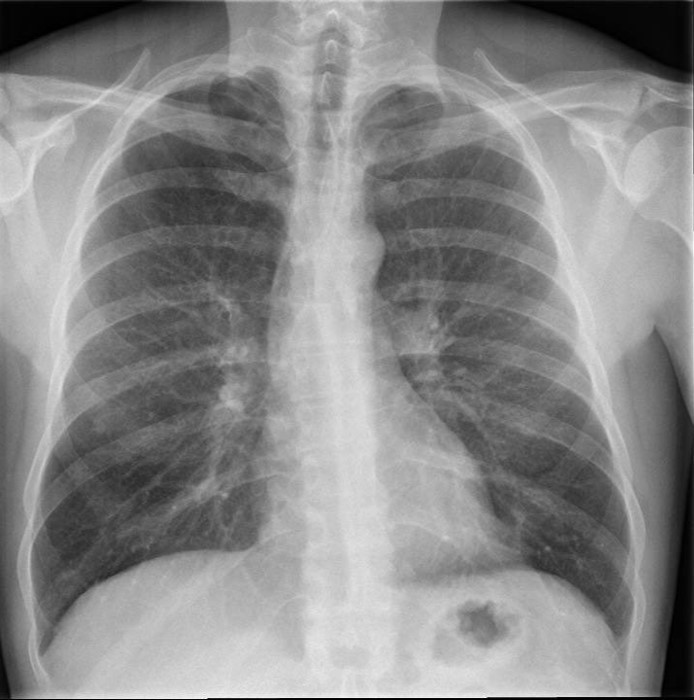

L’électrocardiogramme (ECG)et la radiographie thoracique sont donnés ci-après :

La radiographie thoracique est normale.